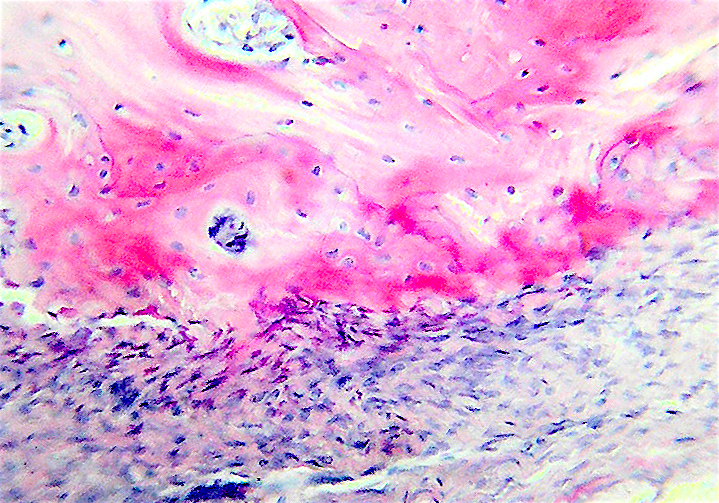

Инес в 1970 году открыла, что в физиологических концентрациях соли кальция должны выпадать в осадок и вода уходить из клеток.

В тканях присутствуют ингибиторы кальцификации.

Это пирофосфаты, фосфонаты, дифосфонаты.

Поэтому в кальцинации участвуют ферменты которыи? блокирует дифосфонат.

Это ингибиторы кальцификации.

Пузырьки образуются из митохондриий и выбрасываются клетками, они обызвествляют кости, в них образуются игольчатые отложения.

Они ферментативно активны.

Первым это открыл Андерсон в хрящевой ткани в 1976, наблюдая процесс обызвествления хряща.